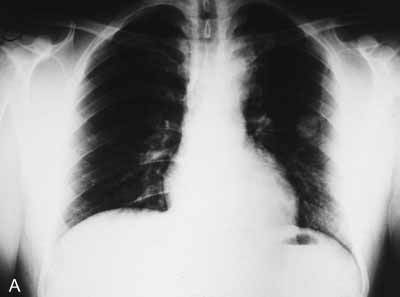

Chest radiography is the primary imaging modality for a solitary lung nodule (Figure 2A). Chest films can delineate nodule size, margin characteristics, calcification, and growth rate. All of these features can help predict the likelihood of malignancy.

Growth rate. Whenever possible, obtain all previous radiographs to determine the length of time the lesion has been present and whether there has been any change in size (Figure 2B). Keep in mind that some malignant lesions appear to be unchanged even after 2 years.11-13